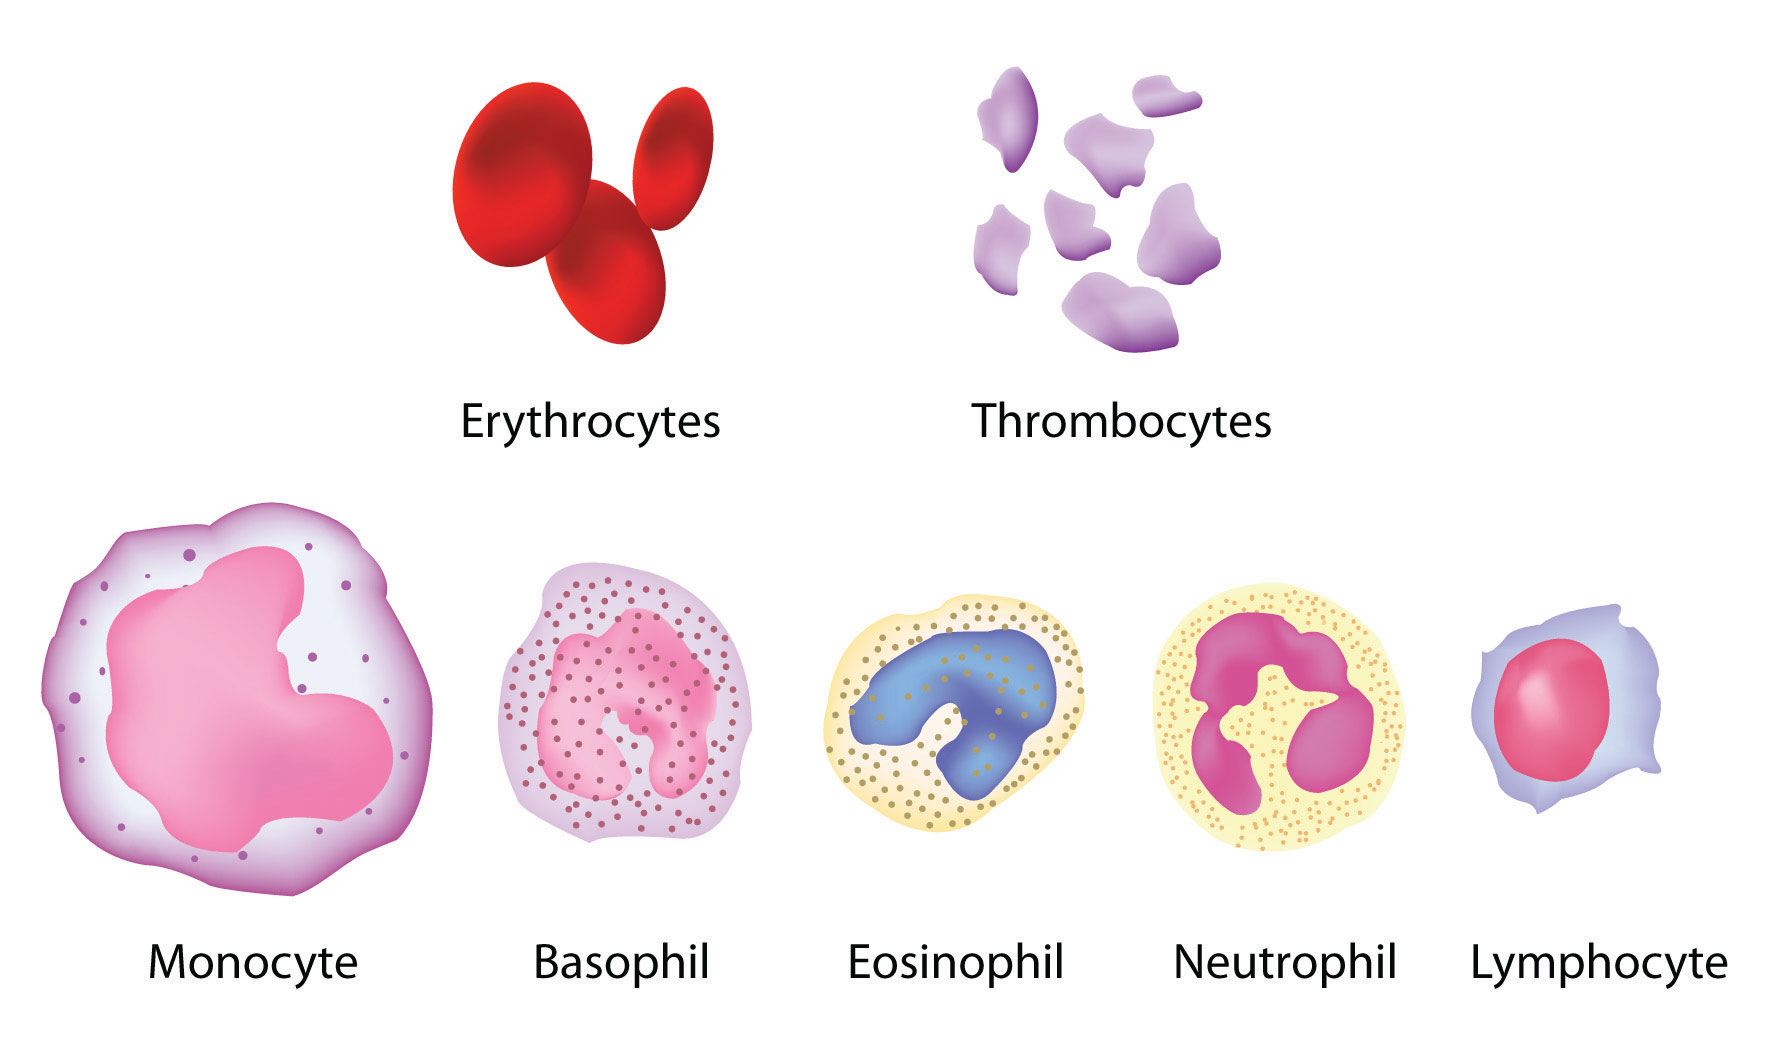

6. The Circulatory System (human)

- Components of blood and their functions (Red blood cell, white blood cell, platelets and plasma (blood groups)